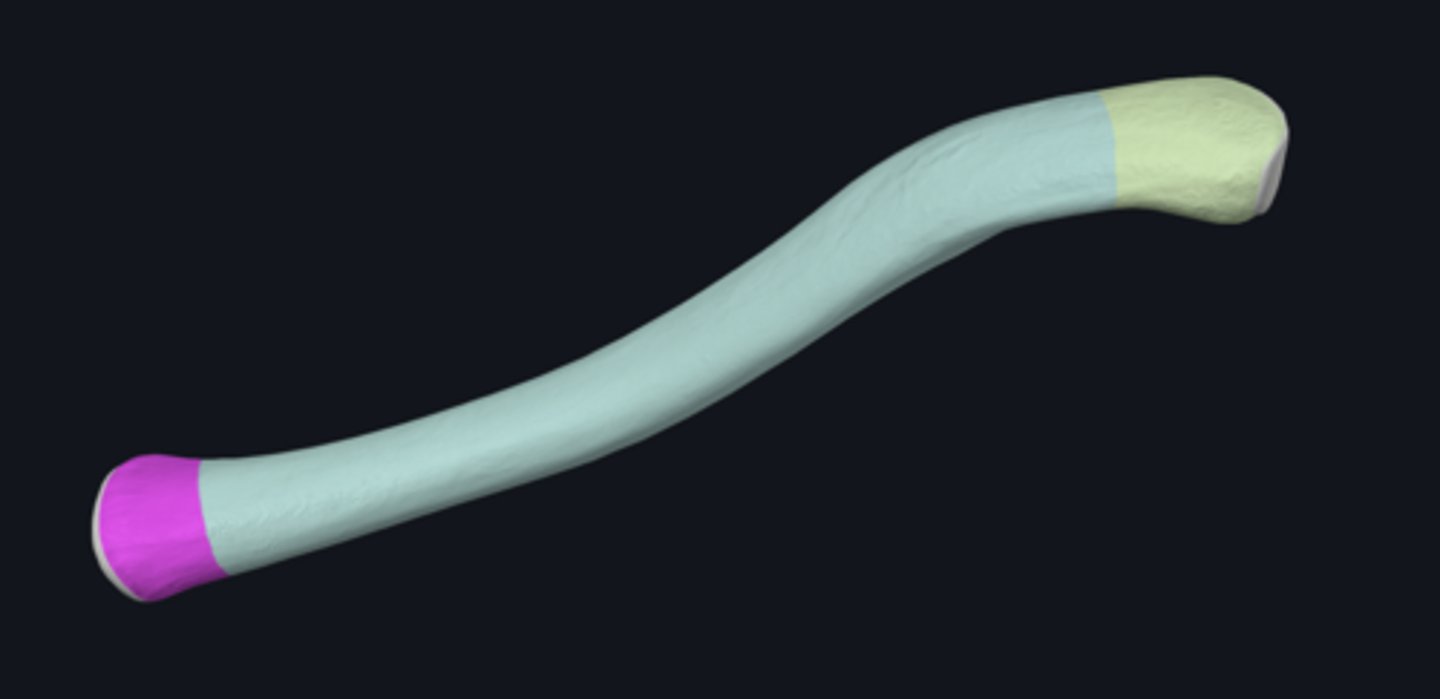

bones of the upper limb

anterior border of radius

anterior surface of radius

carpal articular surface

interosseous border of radius

lateral surface of radius

posterior border of radius

posterior surface of radius

articular circumference of head of radius

articular facet of head of radius

dorsal radial tubercle

grooves for extensor tendons

head of radius

lunate articular facet of radius

neck of radius